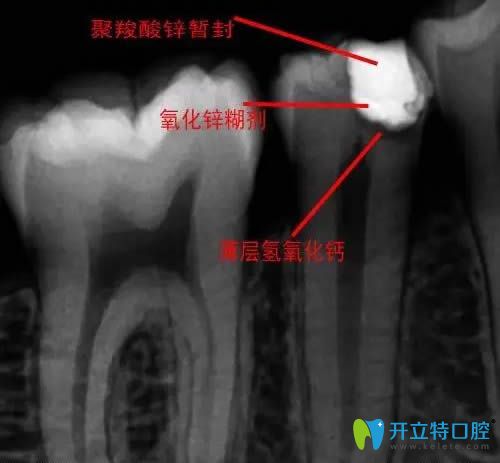

牙齒蓋髓術(shù)圖解

一種保存牙齒活髓的方法,是把蓋髓劑覆蓋在即將暴露或已穿露的牙髓部位,使其創(chuàng)面上的病變消除。常用的蓋髓劑有氫氧化鈣制劑或氧化鋅丁香油糊劑等,均有較強(qiáng)的殺菌、抑菌能力和滲透作用,可促進(jìn)牙髓組織再生,目的就是為了保存活的牙髓組織保留患牙。通俗來(lái)講,就像是把草藥敷在傷口上,這樣既能療傷又能避免傷口感染。

直接蓋髓術(shù)拍片圖解